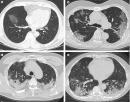

- 大陆疯传原始毒株重现 医护曝恐怖 “ 白肺 ” 照片 (图/视频)2022-12-27时事新闻白肺 , 中国大陆 , 疫情, 原始毒株, 确诊者中国大陆各省近日染疫和死亡人数飙升,多地火葬场不堪负荷。